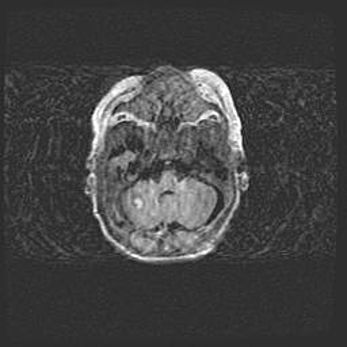

Неполная лизэнцефалия (пахигирия). Открытая гидроцефалия.

Возраст: 17 дней

Вес: 3110 г

Пол: мужской

Окружность головы: 33,5 см

Срок гестации: 35-36 недель

Лизэнцефалия—недоразвитие корковой пластинки и мозговых извилин в результате нарушения миграции нейронов коры. Поверхность мозговых полушарий гладкая. Микроскопически выявляется отсутствие нормальных слоев коры и скопление групп нейронов в подкорковом белом веществе.

Пахигирия—уменьшение числа вторичных извилин. В пораженном полушарии нервные клетки образуют толстый недифференцированный слой с неправильно расположенными нервными волокнами и группами гетеротопных клеток. Нервные клетки незрелые. Белое вещество истончено. При этом нередко аномально развит корково-спинномозговой путь.